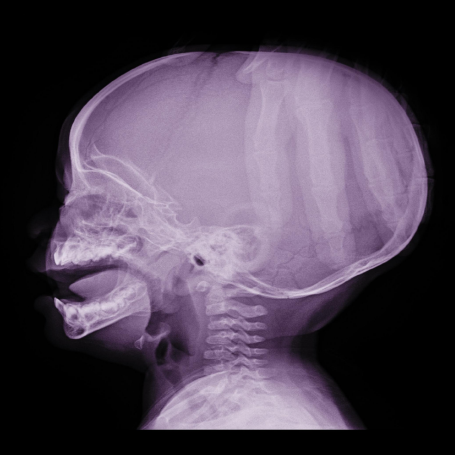

Diagnóstico: Se realiza mediante evaluación clínica de síntomas como dolor de cabeza, vómito, alteraciones de la marcha o visión. Se confirma con estudios de imagen como tomografía computarizada (TAC) o resonancia magnética (RM), que muestran la dilatación ventricular y la causa.